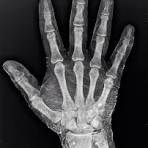

الأشعة السينية لا تُنتج صورة لأنها “تكشف العظام” بحد ذاتها، بل لأن تفاعلها مع المادة يعتمد بشدة على العدد الذري. ذرات الكالسيوم في العظام تمتلك عددًا ذريًا أعلى من ذرات العناصر المكوِّنة للأنسجة الرخوة، لذلك تمتص الأشعة السينية بكفاءة أكبر. هذا الامتصاص غير المتساوي يخلق تباينًا حادًا: مناطق داكنة حيث تمر الأشعة، ومناطق فاتحة حيث تُمتص. الفكرة نفسها هي التي سمحت لاحقًا بتطوير مواد تباين طبية وبتحسين كواشف الأشعة، محوِّلة ظاهرة فيزيائية بسيطة إلى أداة تشخيصية غيّرت الطب جذريًا.